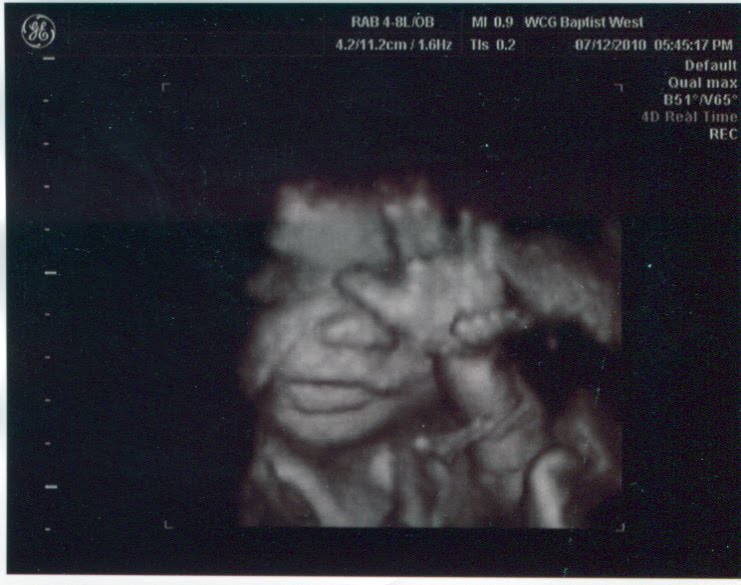

Now you know why I’ve been so quiet here lately: It’s been…